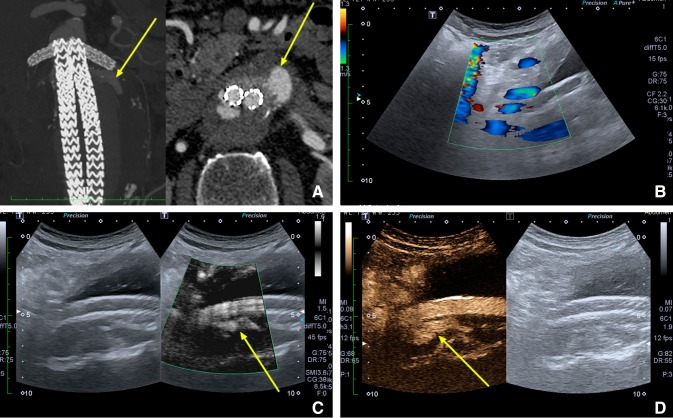

Fig. 2.

A type I endoleak (yellow arrow) according to four different imaging methods of an abdominal aortic aneurysm: A Computed Tomography Angiography, B Color Doppler Ultrasound, C monochrome Superb Micro-vascular Imaging, D Contrast-Enhanced Ultrasound